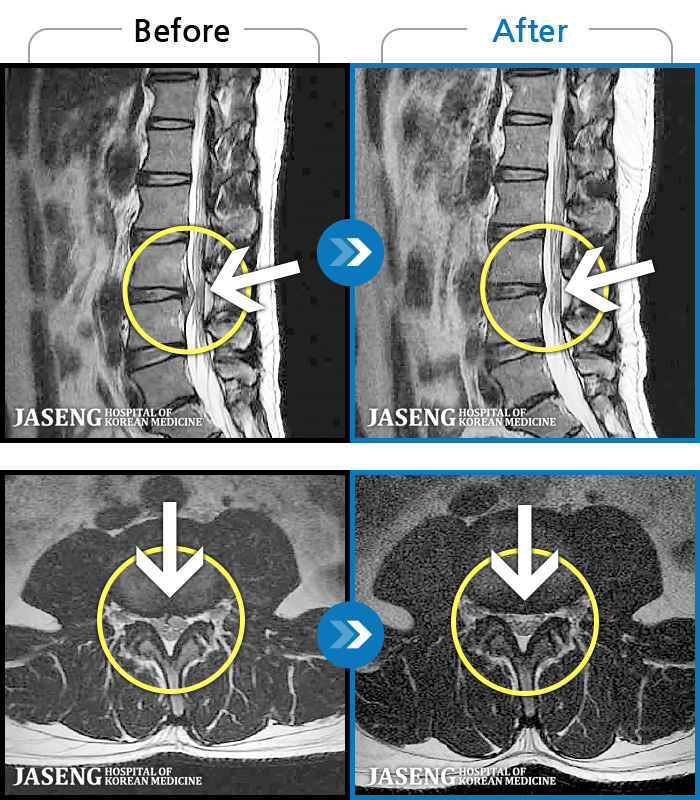

[ؿ] 24.10.10~25.04.23